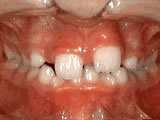

Phase One

Patient's parents were concerned about both aesthetics and the health of the erupting permanent teeth when they brought him to the orthodontist at age eight. The lower front teeth were crowded and touching the palate, and the upper front teeth were extremely displaced from their normal positions. After 12 months of Phase One treatment with an expander and partial braces, patient's appearance and dental function were vastly improved.